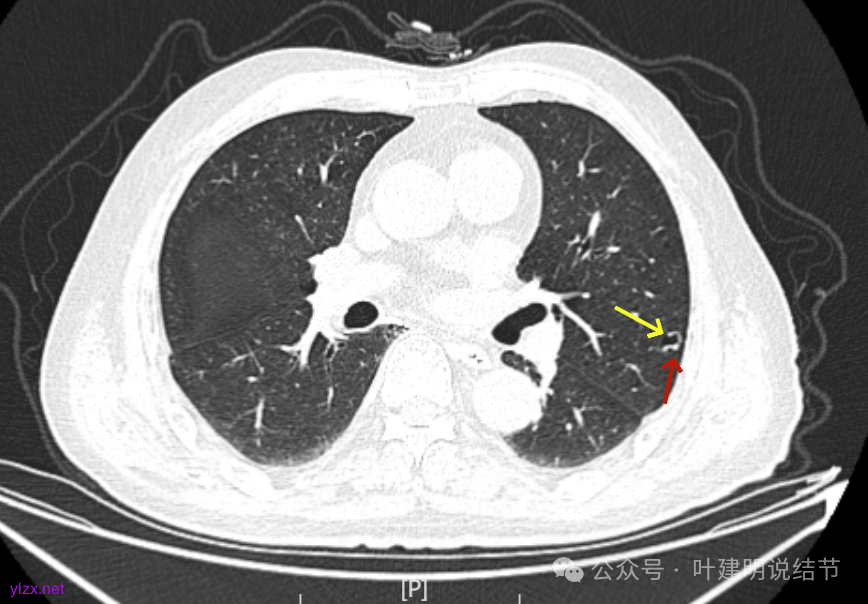

先来看2025年1月的影像:

病灶出现,有少许磨玻璃成分,整体轮廓较清,实性部分较为光滑。

有囊腔,表面不平,部分囊壁是磨玻璃成分。

病灶囊壁稍不均,多密度较高,表面欠平。

病灶整体的囊壁稍不均,靠内侧有磨玻璃成分。

囊壁不厚但密度较高。

囊腔内壁稍显不光滑,有少许突起于囊腔内。

上图也见囊腔内壁有突起,此层囊壁大部分呈磨玻璃密度。

边缘区是淡磨,内壁少许突起。

左肺上叶红色这处是囊腔型病灶,囊壁略不均,似有微小血管进入囊壁,对比2023年4月整个囊腔来讲有扩大,需要考虑囊腔型肺癌的可能性大。右侧蓝色的并不是典型囊腔型肺癌的表现,再加上两肺绿色这些慢支肺气肿与肺大泡的影像,右侧的就更加不确切,至少近期不能够考虑右侧也要开刀的事情。其实左侧的主病灶相对于其他表现更典型的囊腔型肺癌来说,由于囊壁密度偏高,也不是百分百必定是肺癌。我的想法还是先等脑梗情况稳定,并且间隔4~6个月复查病灶再有进展在考虑单孔胸腔镜下局部切除就可以。淋巴结可以考虑采样,但一般不至于阳性。破是不会切破的。消融不建议,囊腔灶更难通过穿刺获得病理依据,况且东西在边上,能局部楔切,当然首选手术。意见供参考!